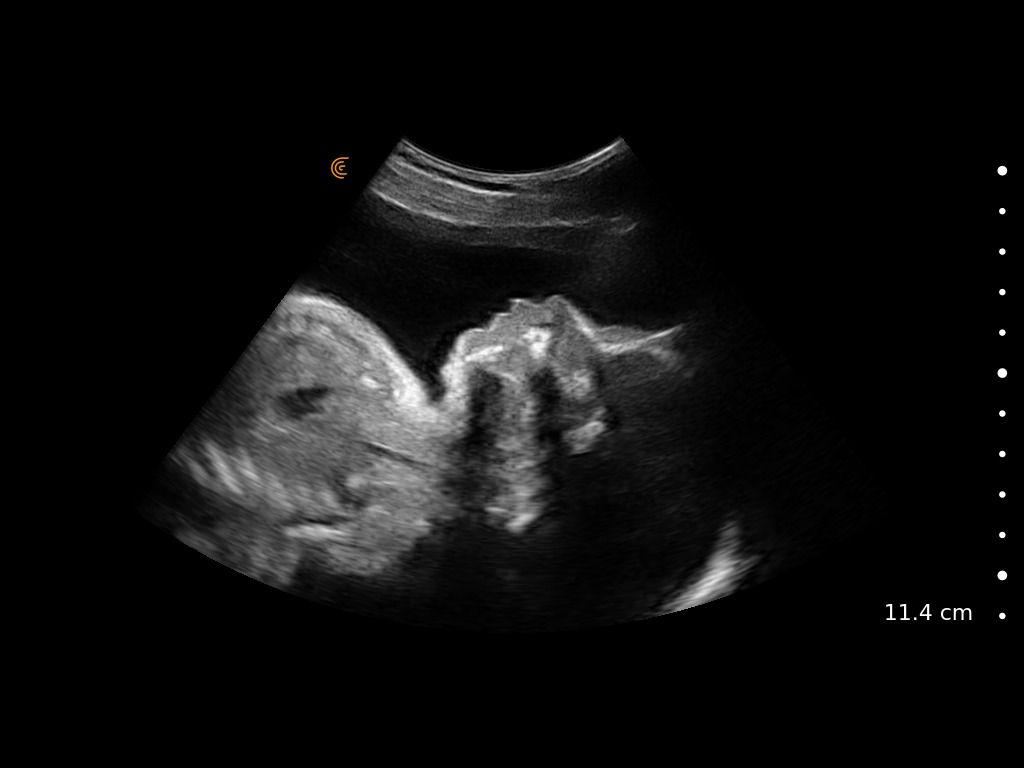

Medical professionals love the high portability, easy of use, and high-definition imaging of the Clarius C3 HD3 multipurpose scanner for full body imaging up to 40 cm. It’s the leading choice for medical professionals looking for premium imaging in an affordable scanner. Artificial intelligence, specialized presets and customizable workflows automatically optimize imaging for a seamless experience.

Applications: Abdominal, Cardiac, Lung, OB/GYN, Superficial

Clinical Images